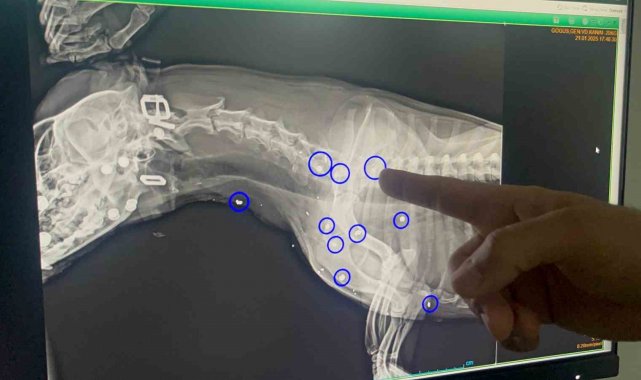

Tepebaşı ilçesi Aşağısöğütönü Mahallesi'nde sahipsiz köpek, hayvan severlerin iddiasına göre 21 Ocak tarihinde av tüfeği benzeri bir silah ile vuruldu. Vücudunun 12 yerine saçma değen ve yaralanan köpek özel bir veteriner kliniğinde tedavi alındı.

"İlk geldiğinde zaten saat 05.00 civarlarında geldi. Karnının tok olduğunu düşündüğümüz için anestezi uygulayamadık. Ertesi gün röntgeni çekildiğinde de 12 yerinde saçma yaraları olduğunu gördük. Hayati organlara çok yakın olduğu için saçmaları ne yazık ki alamadık. Şu anki süreçte de kalbinde bir büyüme olduğu için ne yazık ki anestezi uygulayamıyoruz, sonraki süreçte kurşun yaralarından dolayı zehirlenme var mı diye durumu mutlaka değerlendirip test ve kontrollerini yapacağız".